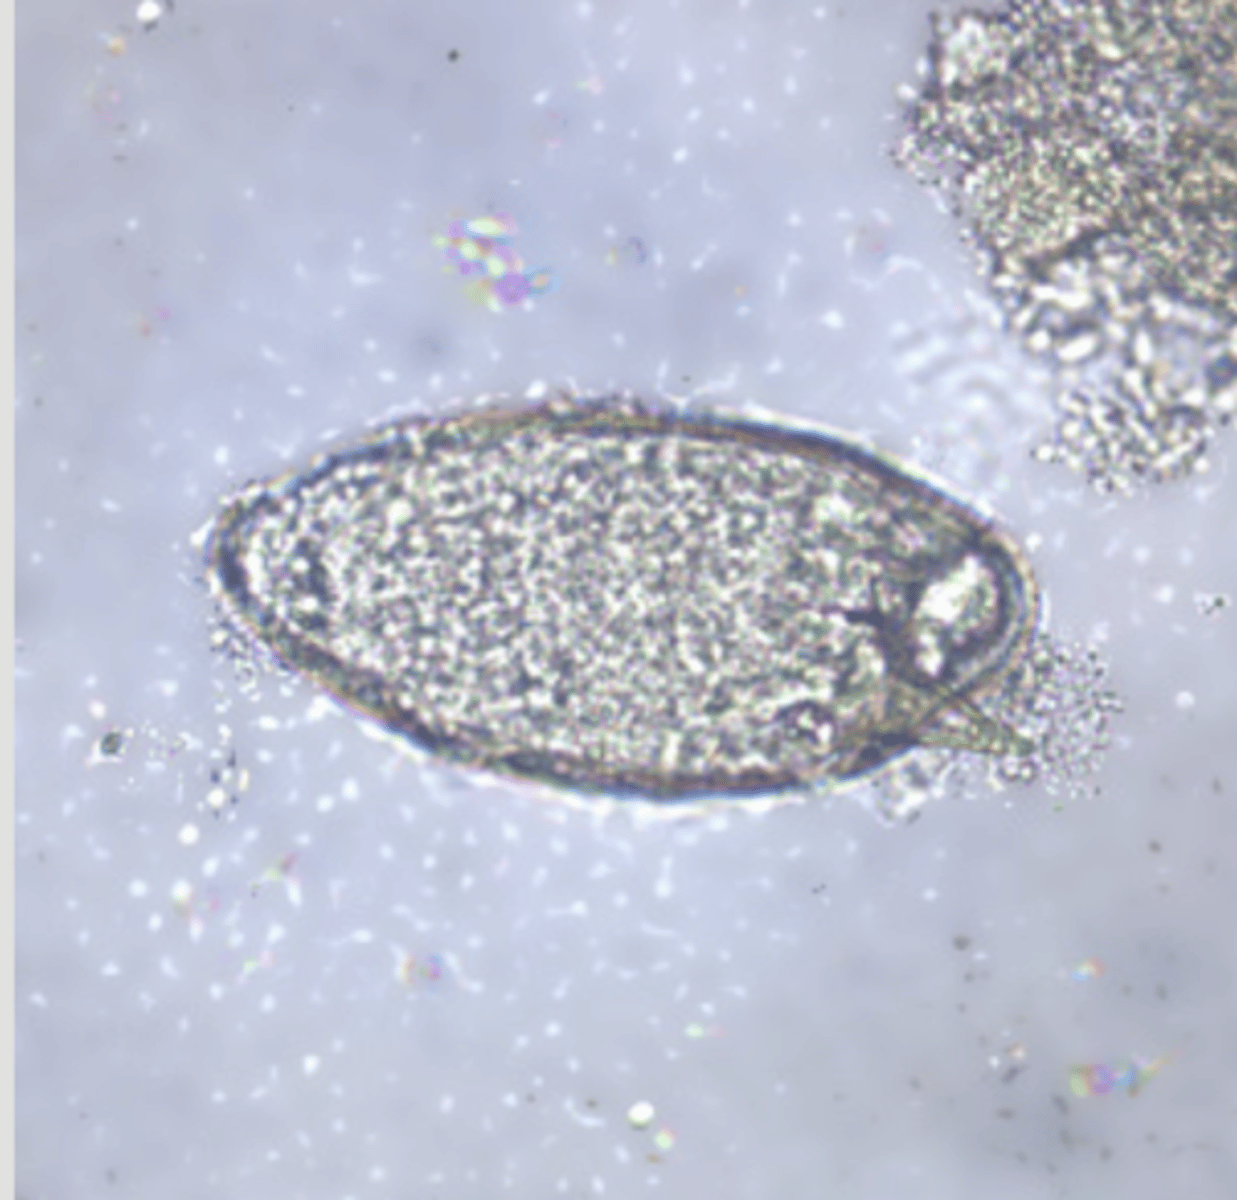

Paragonimus westermani